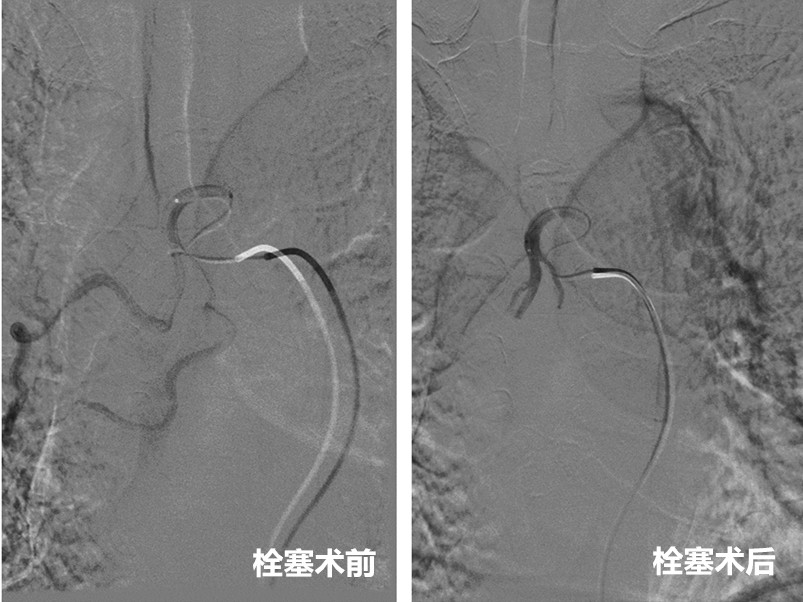

最大的意外发生在手术前。2月22日晚八时许,在上手术台过程中,老王突发大咯血,出血量超过100ml,一口口血痰染红了餐巾纸,这极易造成呼吸道窒息,危及生命。幸好手术已经准备就绪,郑胜立即带领介入团队,消毒、铺巾,迅速而有条不紊的在DSA下为其开展支气管动脉栓塞术。

术中,介入团队顺利穿刺,并借助导丝引导送入微导管,精准栓塞出血点,成功止血。